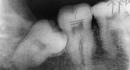

Why do people have baby teeth and adult teeth?